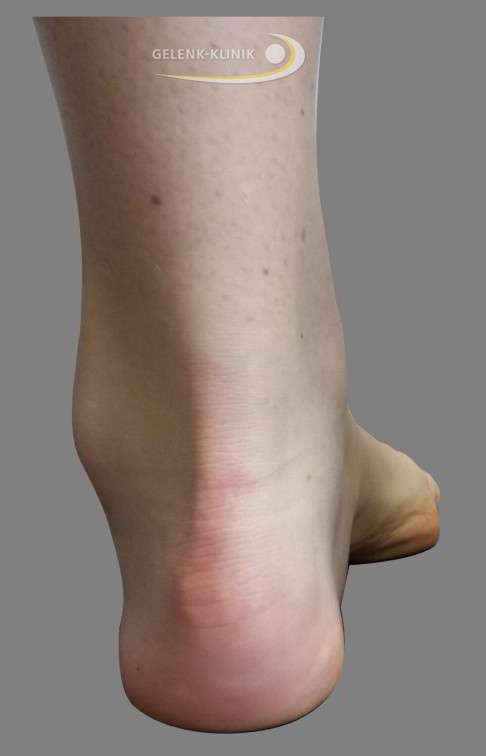

Fersenschmerz und Haglundferse als Folge des Hohlfußes

Der Hohlfuß kann zu einem besonders stark nach hinten hervortretenden Fersenbein führen. In diesem Fall ist der Schuhdruck auf das Fersenbein besonders hoch: Eine schmerzhafte Haglundferse kann die Folge sein. Bei der Haglundferse werden durch den erhöhten mechanischen Druck Schleimbeutel um die Achillessehne gereizt. Auch die Achillessehne selbst und der darunterliegende Knochen werden schmerzhaft gereizt.

Zudem kann diese Steilstellung der Ferse zu Reizungen der Weichteile führen. Hier können Schleimbeutelentzündungen im Bereich des Achillessehnenansatzes entstehen. Überbeine (Exostosen) an der Ferse, auch Haglundexostosen genannt, können daraus resultieren. Durch die Fehlstellung des Rückfußes beim Hohlfuß entstehen an der Ferse besonders häufig chronische Schmerzen.

- Oberer Fersenschmerz und Haglund-Exostose